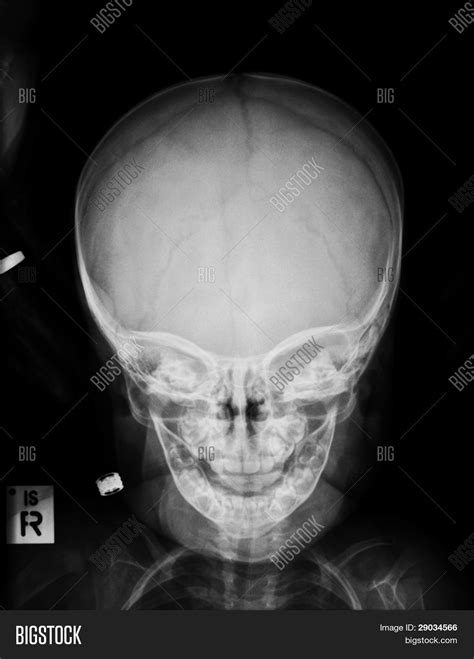

A Baby Skull Xray is a radiographic imaging technique used to visualize the bones of a baby's skull. This non-invasive procedure is essential for diagnosing various conditions, including fractures, deformities, and developmental abnormalities. The X-ray images provide a detailed view of the skull's structure, helping healthcare providers make informed decisions about treatment and care.

Interpreting Baby Skull Xray results requires a trained eye and a deep understanding of pediatric anatomy. Here are some key points to consider:

• Skull Shape: The shape of the skull can provide insights into developmental issues or deformities.

• Sutures: The sutures, or the fibrous joints between the skull bones, should be examined for any signs of premature fusion or separation.